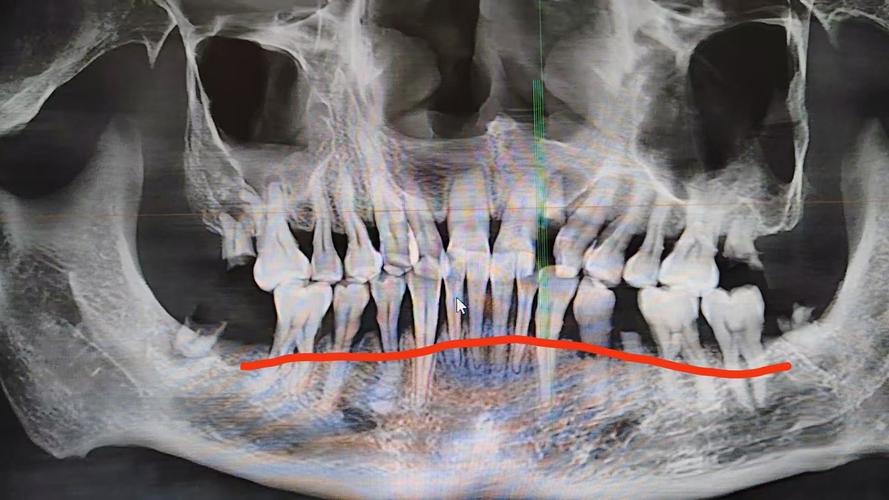

牙槽骨吸收在X光片(主要是根尖片或曲面断层片)上通常表现为以下特征:

- 最直观的表现: X光片上可以看到牙齿根尖周围的牙槽骨(硬骨板)的高度比治疗前或健康邻牙低。

- 骨皮质变薄或模糊: 牙根周围的白色致密骨线(牙槽骨的骨皮质)变得不清晰、变薄甚至中断。

- 牙槽嵴顶高度下降: 牙龈缘对应位置的牙槽骨顶部(牙槽嵴顶)位置降低。

- 骨小梁结构稀疏: 牙槽骨内部的骨小梁(网状结构)变得稀疏、排列紊乱,透光度增加(在X光片上看起来更“黑”一些)。

- 骨透射影: 在吸收严重的区域,可能看到更明显的黑色透射影,表示骨量减少。

- 增宽: 在牙槽骨吸收区域,牙齿与牙槽骨之间的牙周膜间隙可能暂时性或持续性增宽,这通常表示牙齿在移动或受到轻微创伤,是正畸过程中常见的现象,但持续增宽或异常增宽可能提示问题。

- 模糊: 吸收区域的牙周膜间隙边界可能变得模糊不清。

- X光片类型: 根尖片能更清晰地显示单颗牙齿周围的牙槽骨细节,是评估牙槽骨吸收最常用的影像学方法,曲面断层片可以同时显示全口牙槽骨情况,但单颗牙齿的细节不如根尖片清晰。

- 对比评估: 诊断牙槽骨吸收需要与治疗前的X光片进行对比,才能确定是否有吸收及其程度,单凭一张片子有时难以准确判断是治疗引起的还是原有牙周问题的发展。